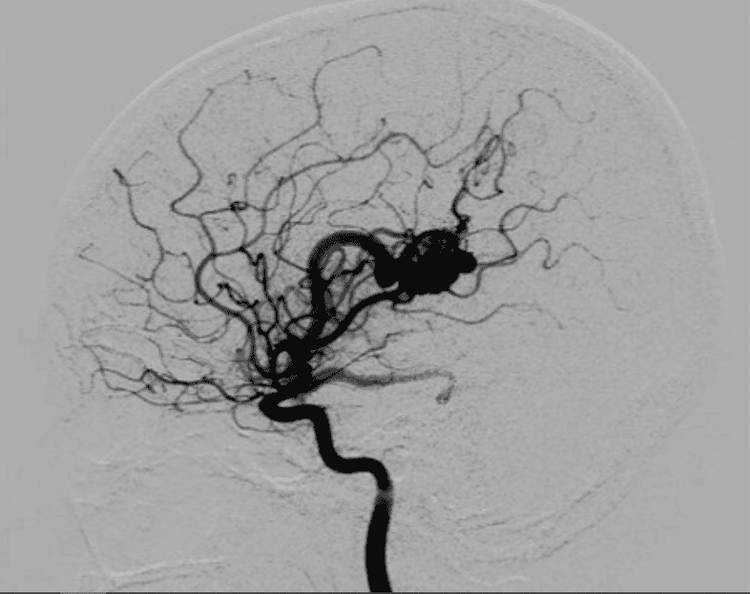

Hình ảnh mạch mãu não của bệnh nhân trên kết quả chụp mạch

Chụp mạch máu cộng hưởng từ MRA thường ít sử dụng trong các trường hợp cấp cứu vì thời gian chụp lâu hơn các kỹ thuật khác. Tuy nhiên chụp MRA đặc biệt hữu ích trong tầm soát các bệnh nhân có nguy cơ mắc các bệnh lý mạch máu, đặc biệt là phình, hẹp, tắc mạch máu não, nhồi máu cơ tim. Rất nhiều bệnh nhân đã được cứu sống vì được tầm soát bằng chụp MRA và được điều trị kịp thời.